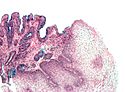

Squamous papilloma of the esophagus